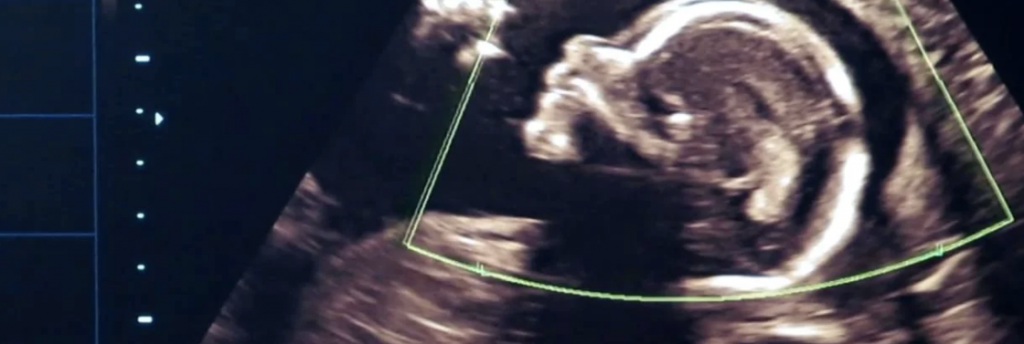

Основным способом выявления этой патологии является ультразвуковое обследование. Именно с его помощью можно установить присутствие зародыша в плодном яйце и его нормальное развитие. При нормальной беременности эмбрион не видно в среднем до 6-7 недели после зачатия, поэтому на этом этапе косвенными признаками патологии могут служить падение уровня ХГЧ в крови или дефицит прогестерона.

Объективную информацию о беременности малого срока дает ультразвуковое исследование. Первое УЗИ проводится через 23-25 дней после переноса эмбрионов; задача на этом этапе – убедиться в том, что беременность маточная (внематочная тоже возможна!) и располагается в матке правильно. Также можно увидеть, нет ли гематом (кровоизлияний) в плодном яйце.

На этом этапе можно и не увидеть эмбрион; он еще очень мал и может не визуализироваться ультразвуком. Для уверенной визуализации эмбриона, а также желточного мешка и амниотической оболочки делают второе УЗИ – на сроке 35 дней после переноса. Если на этом УЗИ эмбрион не визуализируется, это повод для внимательного изучения ситуации. Обычно исследование повторяют через 3-5 дней и уже тогда диагносцируют замершую беременность (если эмбрион не был визуализирован ни разу, говорят об анэмбрионии). Бывает и так, что эмбрион визуализирован, но через некоторое время сердцебиение перестало регистрироваться. Остановка в развитии может происходить на долее поздней стадии.